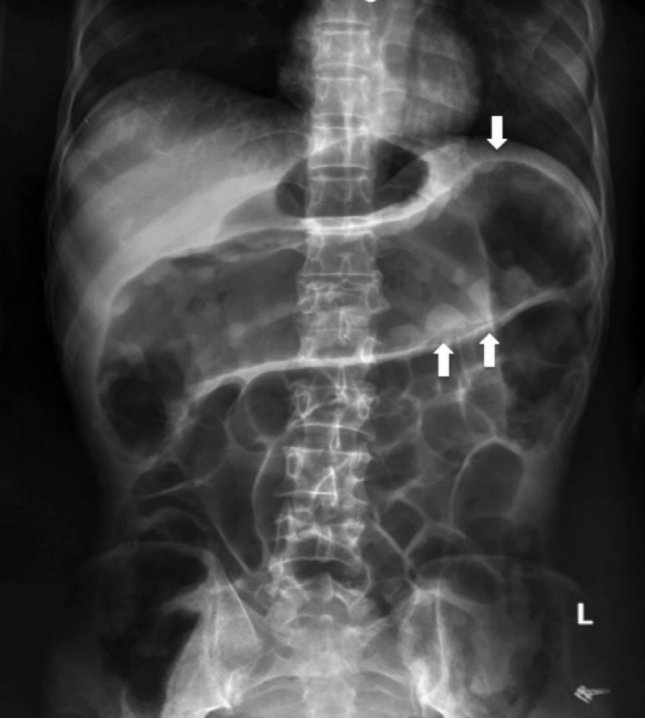

入院检查:血压80/60 mm Hg,脉搏

150次/分,有脱水征,腹部查体无明显异常。仰卧位腹部X线检查示横结肠扩张(图1)。

图1 横结肠扩张,左半可见“拇指印”